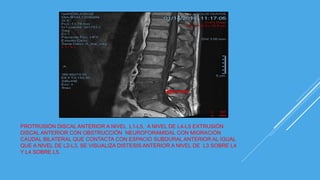

RMN

PROTRUSIÓN DISCAL ANTERIOR A NIVEL L1-L5, A NIVEL DE L4-L5 EXTRUSIÓN

DISCAL ANTERIOR CON OBSTRUCCIÓN NEUROFORAMIDAL CON MIGRACIÓN

CAUDAL BILATERAL QUE CONTACTA CON ESPACIO SUBDURAL ANTERIOR AL IGUAL

QUE A NIVEL DE L2-L3, SE VISUALIZA DISTESIS ANTERIOR A NIVEL DE L3 SOBRE L4

Y L4 SOBRE L5.